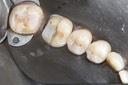

Alan Chinn #4-5 pre-op

Alan Chinn #4-5 caries removal

Alan Chinn #4-5 prep